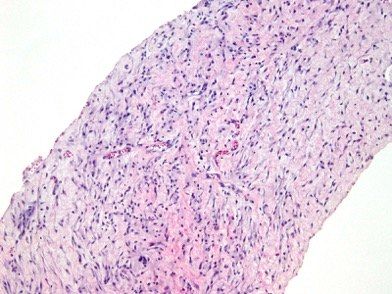

Figure 2. Histologic section of the tissue sample showing myofibroblasts in a myxoid background.

Biopsies of the peritoneal and hepatic nodules and omentum confirmed the diagnosis of inflammatory myofibroblastic tumor characterized by spindled myofibroblasts in a myxoid background and inflammatory infiltrate composed of lymphocytes, eosinophils and mast cells (Figure 2). The immunohistochemical stain was diffusely positive for actin (Figure 3) and focally positive for desmin. The immunohistochemical stains for S100, ALK-1, EMA, CAM5.2, and AE1/AE3 were negative.